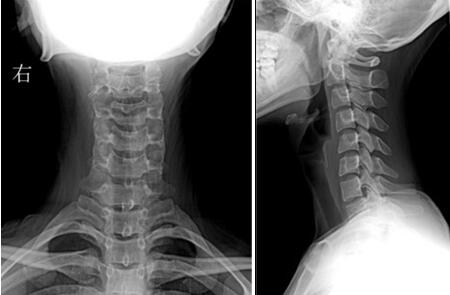

(张女士DR检查示颈椎生理曲度变直,各颈椎椎体骨质完整,边缘清晰,未见增生或破坏,各颈椎椎间隙、椎间孔未见变窄。)

细问得知,张女士和当下不少年轻人一样,特别喜欢玩手机,是一个“低头族”。平日里她常常用手机看电影和视频,尤其喜欢以“葛优躺”的姿势躺在沙发上看,一看就是一两个小时。久而久之,张女士得了头晕、颈痛的病,已严重影响到她的日常生活,这才到医院进一步治疗。为明确诊断,门诊为张女士进行颈部DR检查,提示C4-5椎体不稳。